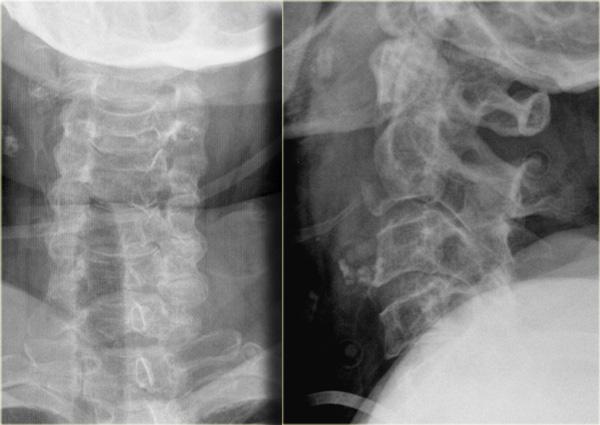

Bên trái là hình ảnh của một nam giới 20 tuổi bị tai nạn xe cơ giới lật xe.

Các dấu hiệu trên X-quang bao gồm:

- Tăng gấp tại mức C4-C5 với khoang gian gai rộng ra

- Trật khớp tại mức C4-C5 với khoảng trượt khoảng 25% (tức là di lệch ra trước 25% đường kính trước-sau của thân đốt sống)

- Mất thẳng hàng của các mỏm gai trên phim thẳng (AP), chỉ có thể xảy ra do chấn thương xoay. Mỏm gai bị tổn thương hướng về phía bên bị tổn thương

- Do xoay, các mỏm gai của C4 và C5 trông ngắn hơn trên phim nghiêng

CT xác nhận trật khớp một bên.

Khớp mặt bên đối diện chỉ bị giãn cách.